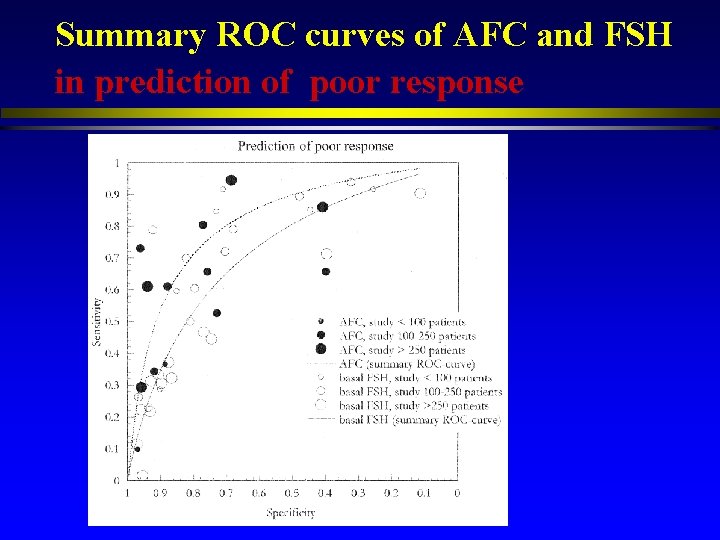

Summary ROC curves of AFC and FSH in prediction of poor response